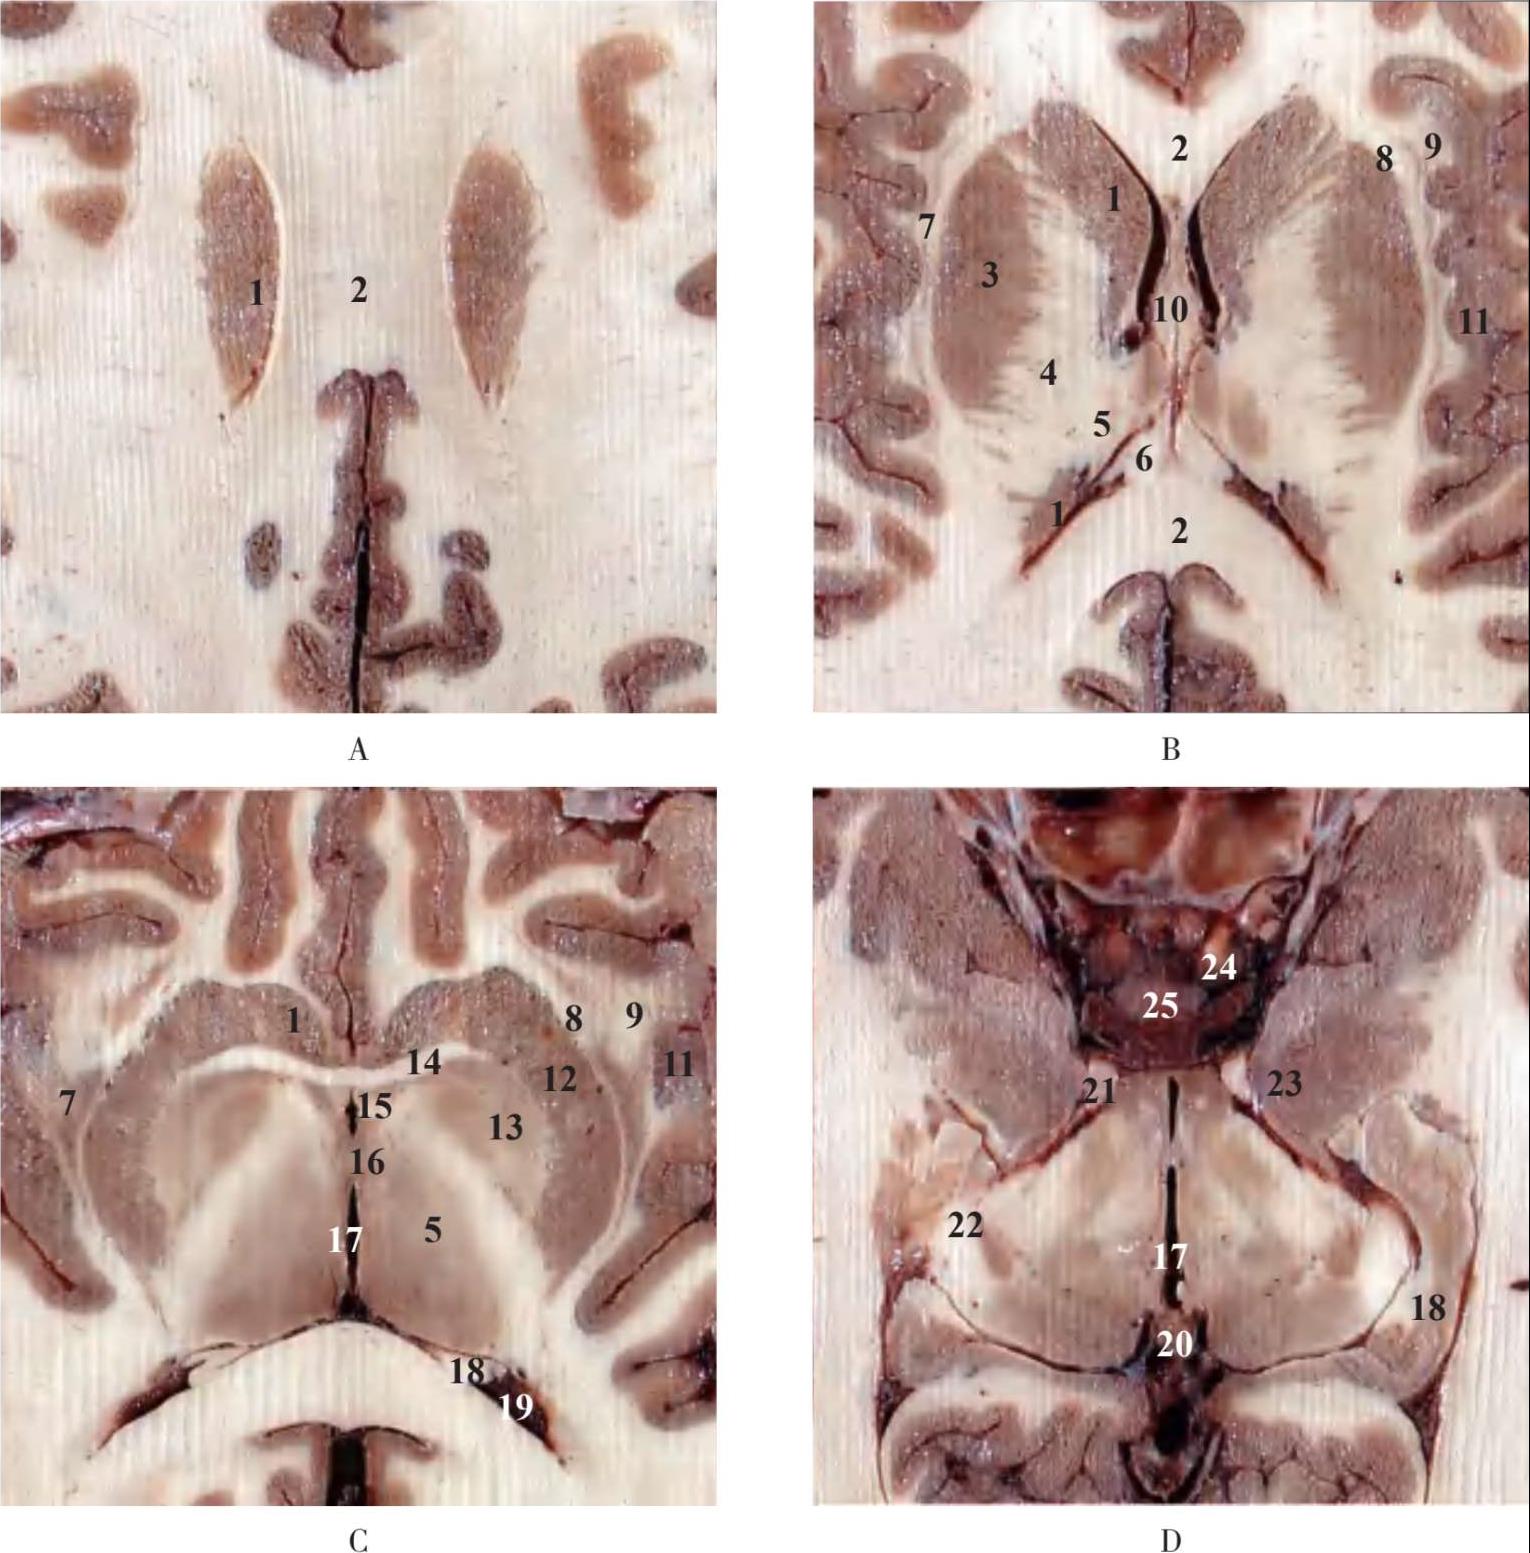

1.尾状核 caudate nucleus;2.胼胝体 corpus callosum;3.豆状核 lentiform nucleus;4.内囊 internal capsule;5.丘脑thalamus;6.穹隆 fornix;7.屏状核 claus trum;8.外囊 external capsule;9.最外囊 exterme capsule;10.透明隔 transparent septum;11.岛叶 insular lobe;12.纹状核壳 putamen;13.苍白球 globus pallidus;14.前连合 anterior commissure;15.穹隆柱 column of fornix;16.中间块 massa intermedia;17.第三脑室 third ventricle;18.海马 hippocampus;19.第四脑室 fourth ventricle;20.松果体 pineal body;21.动眼神经 oculomotor nerve;22.外侧膝状体 lateral geniculate body;23.钩回 uncus;24.颈内动脉 internal carotid artery;25.垂体 pituitary gland

图2-8 水平断层示脑内主要结构